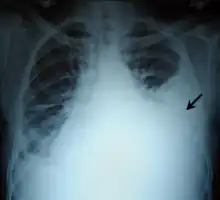

A pleural effusion as seen on lateral upright chest x-ray- Pleural effusion as seen behind the heart.[17]

Massive pleural effusion, later proven to be hemothorax in a South Indian male.